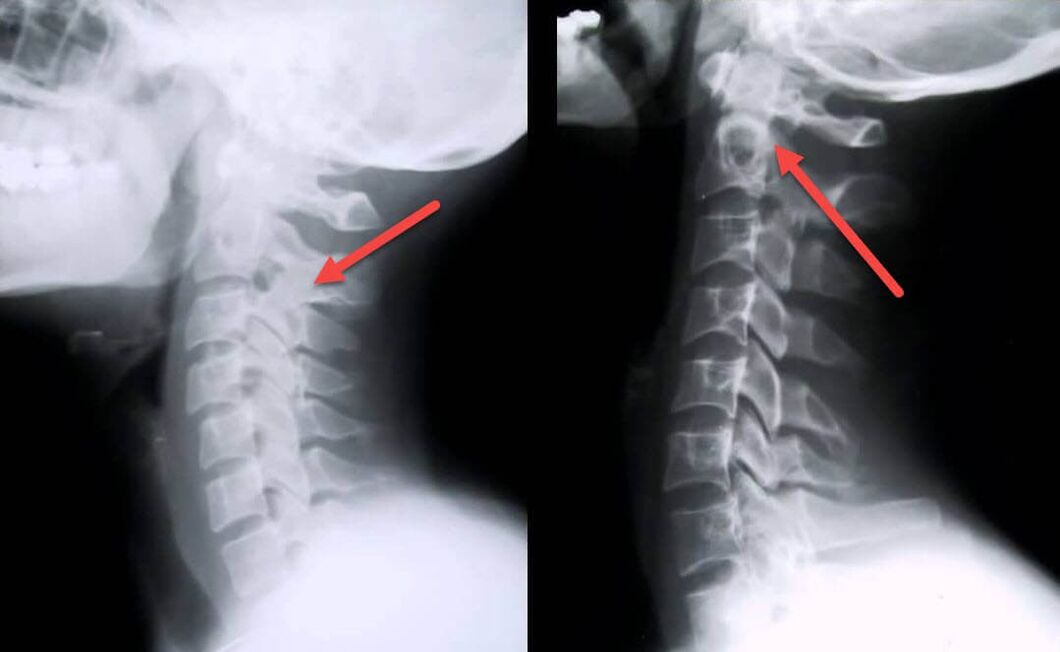

Najbardziej pouczającą procedurą diagnostyczną jest radiografia. Patologie pierwszego stopnia odpowiadają 1. lub 2. etapowi radiologicznemu. Powstałe obrazy wizualizują typowe objawy choroby.

| Etapy rentgenowskie osteochondrozy szyjnej pierwszego stopnia | Znaki charakterystyczne |

|---|---|

| Etap 1 | Niewielkie zmiany krzywizny kręgosłupa w odcinku szyjnym, wpływające na jeden lub więcej segmentów |

| Etap 2 | Nieznaczne pogrubienie krążków międzykręgowych, deformacja wyrostków kolczystych, wyprostowanie lordozy, niewielkie rozrosty struktur kostnych |